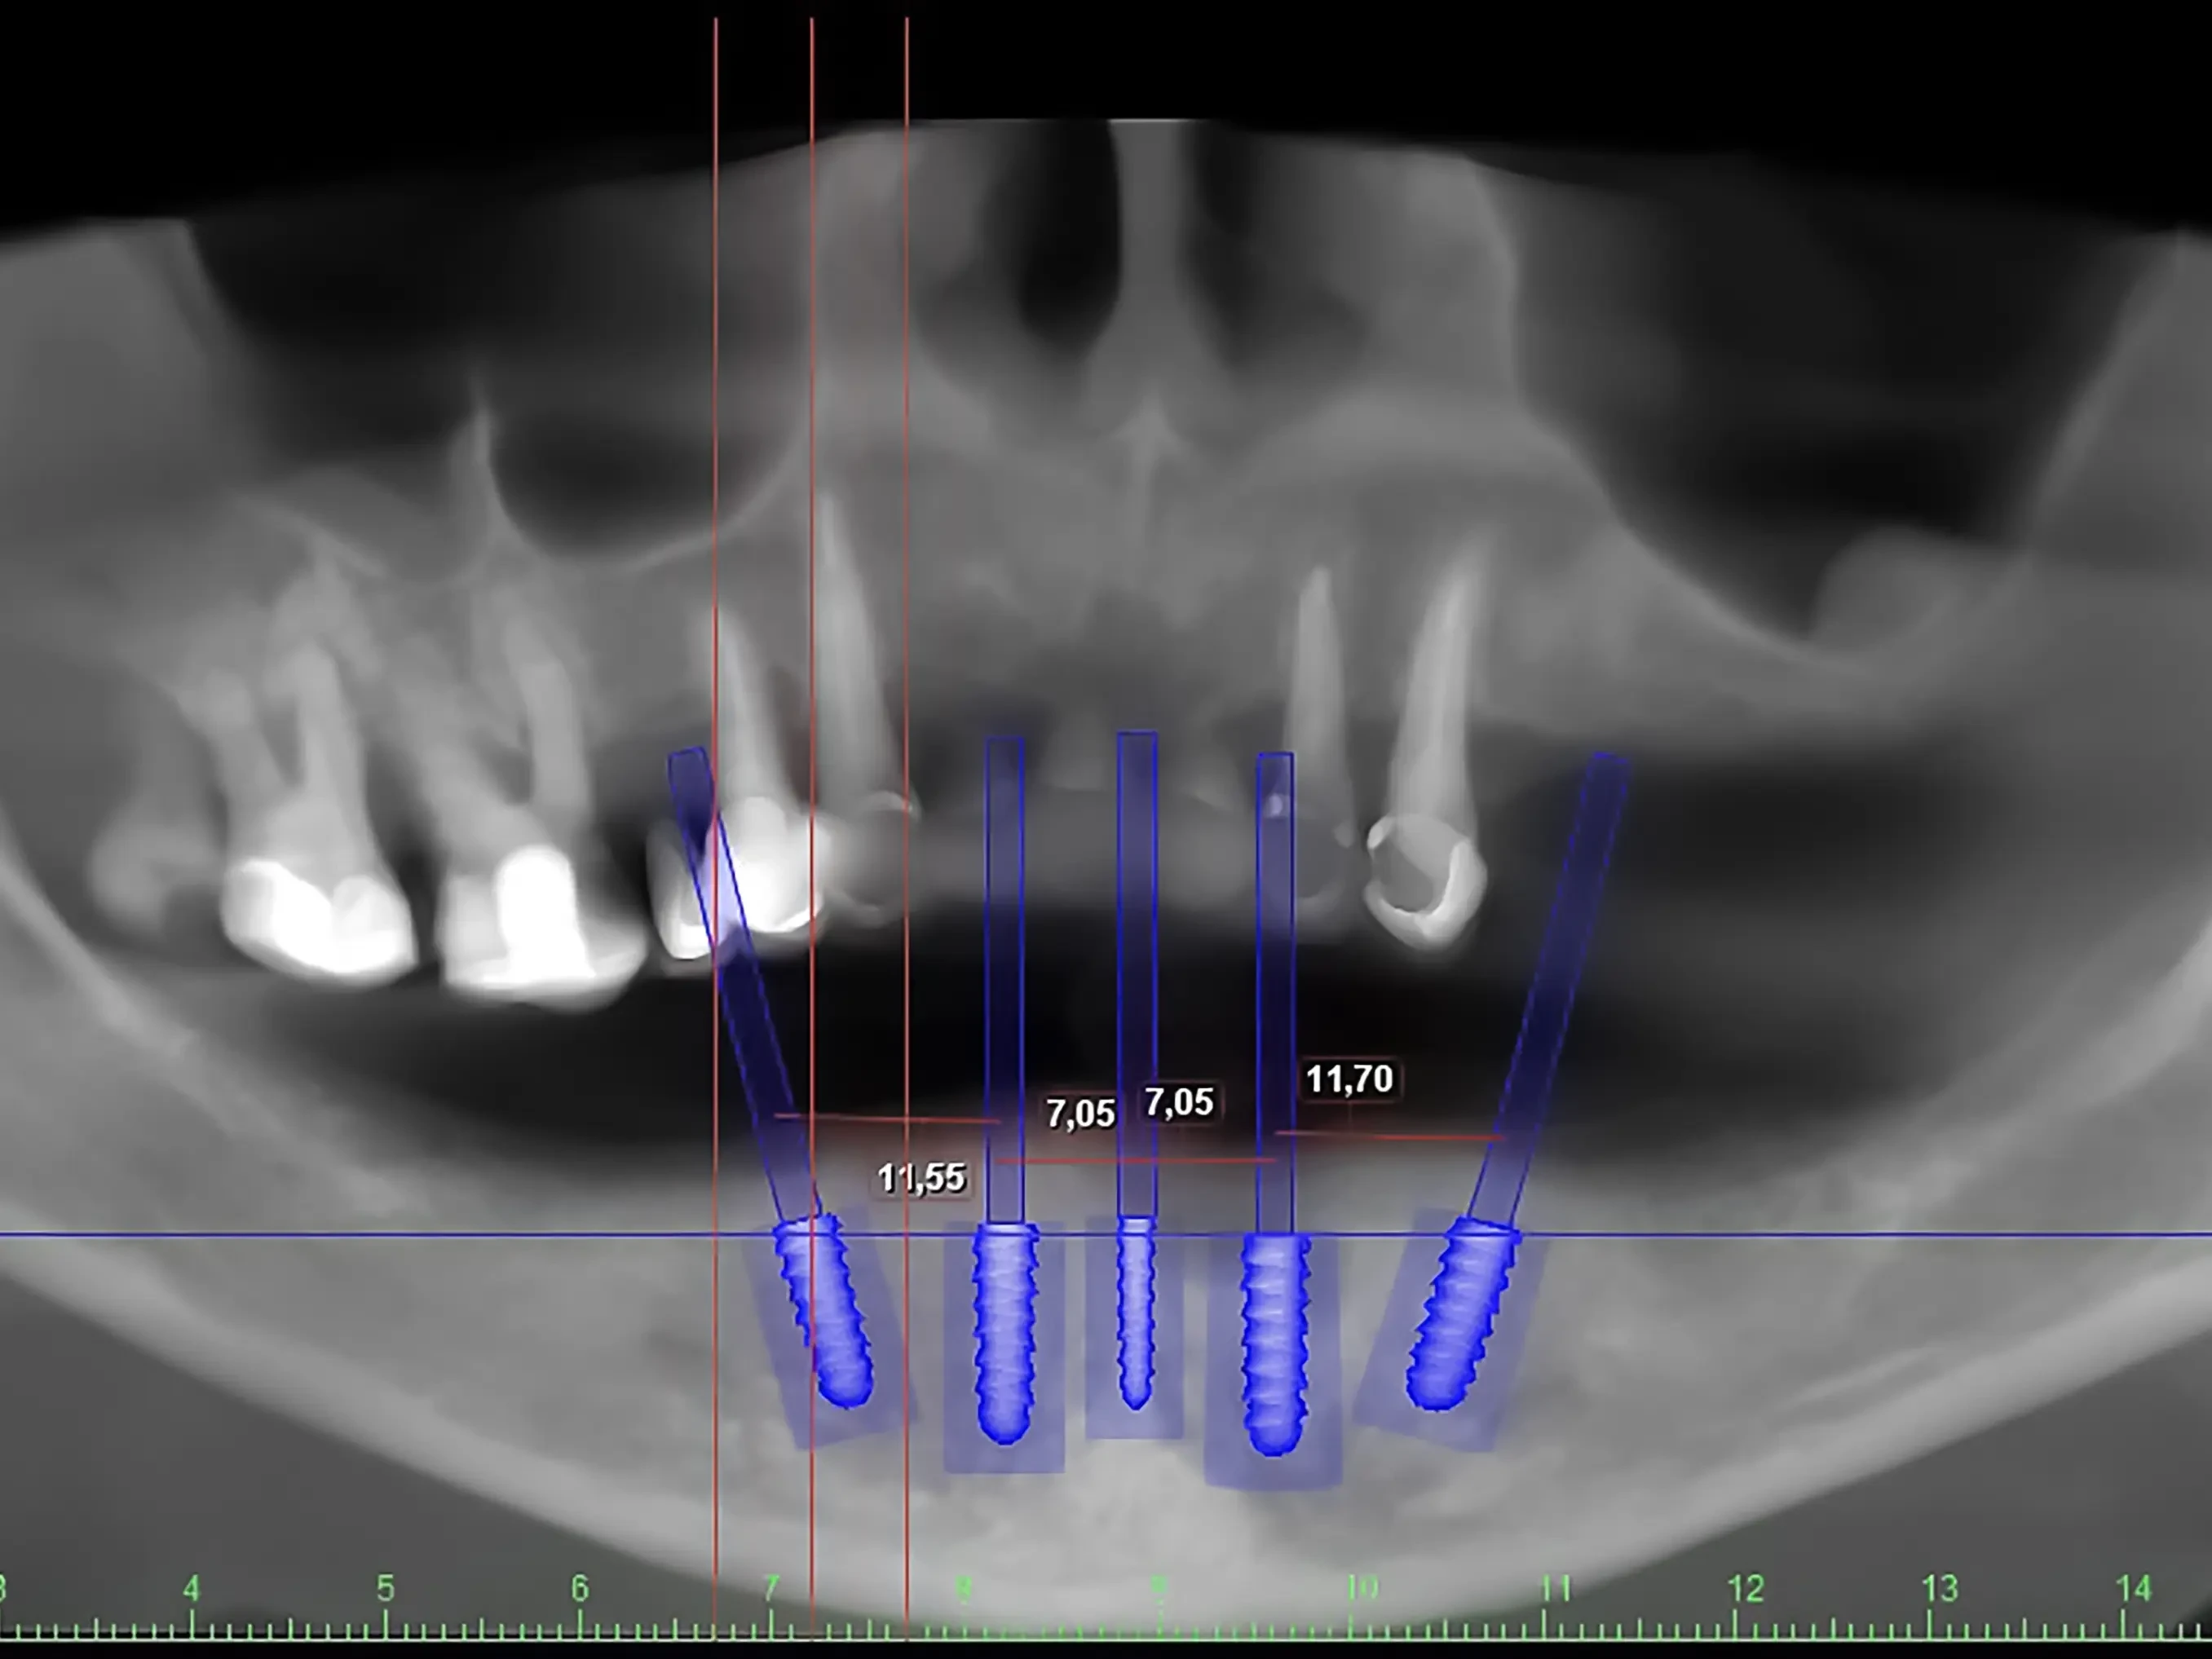

Сложная травма челюсти, долгое отсутствие одного или нескольких зубов, полная потеря зубов в пожилом возрасте – что общего у этих случаев?

Чаще всего во всех этих ситуациях костная ткань челюсти уменьшается в обьеме. Раньше единственным выходом в таком положении была костная пластика. Это сложная процедура, которая восстанавливает кость, но требует больших затрат и долгого восстановления.

Но современная стоматология дает возможность восстановить красивую и здоровую улыбку без этой процедуры – расскажем как.